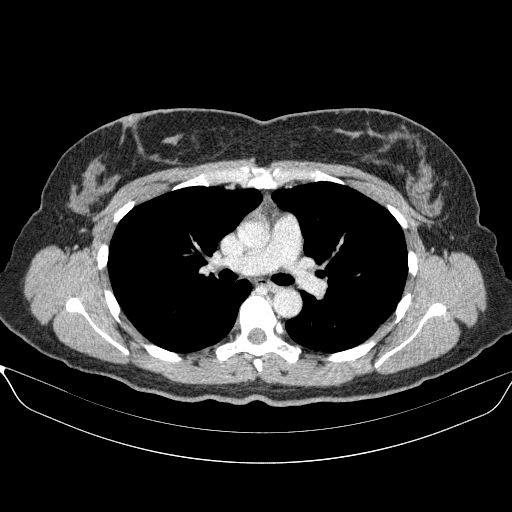

Image Grid

4Γ—3 grid: Rows show different image types (Original NATIVE, Reconstructed NATIVE, Original VENOUS, Generated VENOUS), Columns show windowing techniques (No Window, Lung Window, Mediastinum Window)

Original VENOUS CT scan

Full window (WL 1023.5, WW 4095 β†’ Low βˆ’1024, High +3071)

Lung window (WL -600, WW 1500 β†’ Low βˆ’1350, High +150)